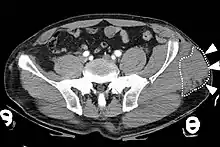

Image is of a computed tomography (CT) image of a Morel-Lavallee lesion.

Computed tomography (CT) image of the pelvis depicting a closed internal degloving injury (Morel-Lavallée lesion). CT is shown in the axial plane. The white dotted lines and white arrows indicate a collection of blood inside the lesion. A fracture of the left iliac wing is also visible on the CT.[10]

Computed tomography

Computed tomography (CT) is important in settings of an emergency or when magnetic resonance imaging is not available.[8] CT will show the presence of a Morel-Lavallée lesion and whether fluid is present.[7] The use of contrast can also help determine if fluid present in a lesion is due to active bleeding.[8]